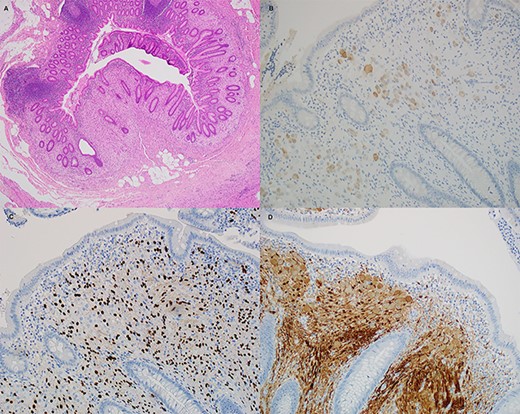

The patient underwent a laparoscopic appendicectomy the following day. Intra-operatively the appendix appeared acutely inflamed and dilated but not perforated, and the base appeared healthy. The procedure was uncomplicated, and the patient was discharged home on Day 2 after recovering well. The histopathology revealed acute suppurative appendicitis with mucosal ulceration. Additionally, there was disordered proliferation of ganglion cells admixed with spindle cells and eosinophils at the proximal margin of the appendix, which after undergoing immunostaining for Neu-N, Sox-10 and S100 an additional diagnosis of benign ganglioneuroma was made (Fig. 2). The patient was discussed at the local general surgery multidisciplinary meeting (MDT), where a decision for no further treatment was made. The patient was counselled to seek medical opinion if he experienced any new symptoms and advised that bowel polyps are a possibility.

Histological sections of the ganglioneuroma. (A) hematoxylin and eosin, (B) Neu-N, (C) Sox10 and (D) S100.